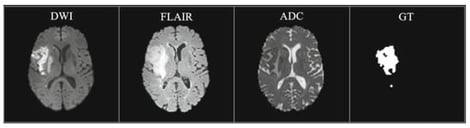

Accurate segmentation of ischemic stroke lesions from multimodal magnetic resonance imaging (MRI) is fundamental for quantitative assessment, treatment planning, and outcome prediction; yet, it remains challenging due to highly heterogeneous lesion morphology, low lesion–background contrast, and substantial variability across scanners and protocols. This work introduces Tri-UNetX-2D, a large-kernel and scale-aware 2D convolutional network with explicit boundary refinement for automated ischemic stroke lesion segmentation from DWI, ADC, and FLAIR MRI. The architecture is built on a compact U-shaped encoder–decoder backbone and integrates three key components: first, a Large-Kernel Inception (LKI) module that employs factorized depthwise separable convolutions and dilation to emulate very large receptive fields, enabling efficient long-range context modeling; second, a Scale-Aware Fusion (SAF) unit that learns adaptive weights to fuse encoder and decoder features, dynamically balancing coarse semantic context and fine structural detail; and third, a Boundary Refinement Head (BRH) that provides explicit contour supervision to sharpen lesion borders and reduce boundary error. Squeeze-and-Excitation (SE) attention is embedded within LKI and decoder stages to recalibrate channel responses and emphasize modality-relevant cues, such as DWI-dominant acute core and FLAIR-dominant subacute changes. On the ISLES 2022 multi-center benchmark, Tri-UNetX-2D improves Dice Similarity Coefficient from 0.78 to 0.86, reduces the 95th-percentile Hausdorff distance from 12.4 mm to 8.3 mm, and increases the lesion-wise F1-score from 0.71 to 0.81 compared with a plain 2D U-Net trained under identical conditions. These results demonstrate that the proposed framework achieves competitive performance with substantially lower complexity than typical 3D or ensemble-based models, highlighting its potential for scalable, clinically deployable stroke lesion segmentation.